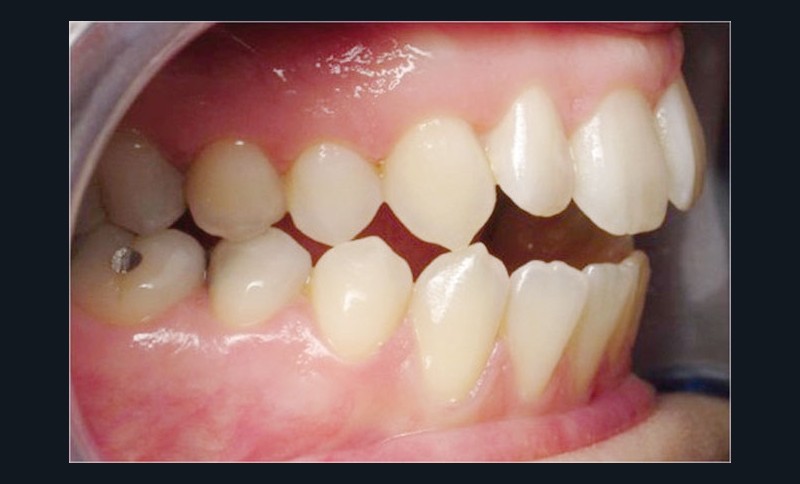

Les empreintes ont été réalisées en sillcone wash technique et adressées au laboratoire Insignia. Actuellement, nous réalisons ces empreintes à l’aide de la caméra intra-orale Lythos et la fiche patient est initialement créée sur la caméra. Le transfert des empreintes au laboratoire est immédiat et le risque d’erreurs considérablement réduit (fig. 4 à 6).